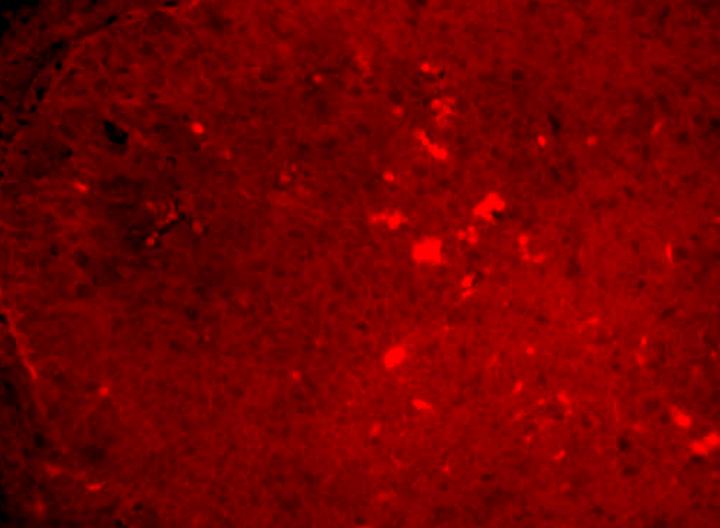

image: A red fluorescent probe detects mRNA translation in mouse lymphoma. Singh et al. find that the oncogene MYC enhances the translation efficiency.

Kamini Singh/Hans-Guido Wendel